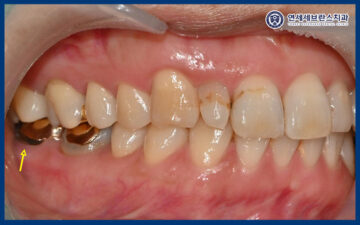

위 환자분께서는

오른쪽 아래 어금니가 불편한데

살려 쓸 수 있는지

궁금해서 본원에 내원해주셨습니다.

잇몸이 내려가면서

치아 뿌리가 드러나 있었고,

그 부위가 잘 관리되지 못해

내부에 충치가 발생한 것을

확인할 수 있었습니다.